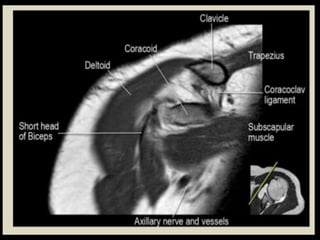

Shoulder

Joint.